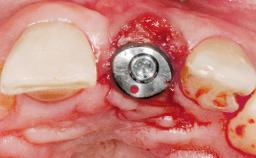

Immediate Placement of an Implant in a Maxillary Left Central Incisor Site

Type of Implants One-Piece

Placement Protocol Immediate implant placement

Tooth Site Maxillary incisor or canine

Socket Morphology Single-root socket

Socket Integrity Damage to one or more bone walls

Bone Volume Damage to one or more socket walls